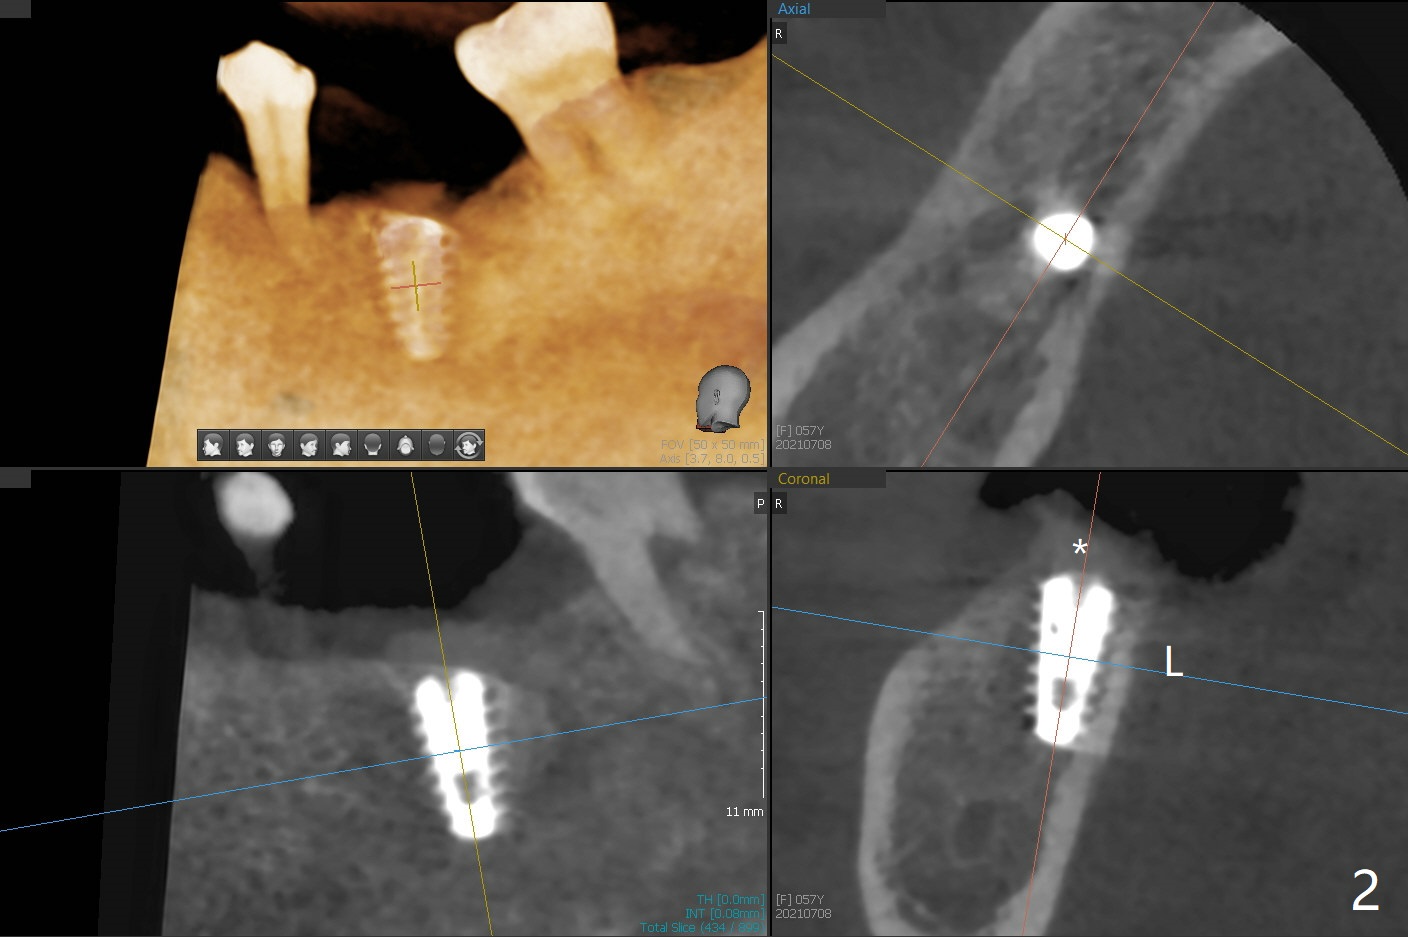

植体取出植骨后十个月,几乎按照导板顺序(除了4.5x10, 4x11.5毫米钻头),植入5x9毫米植体第二条线上缘,植体舌侧好像在牙槽嵴上(图一),临床上植体偏舌侧。放置愈合帽后,置入自体骨,往舌侧塞(图二:*),覆盖GEM Cap,牙周胶水固定,最后牙周敷料。其实植体舌侧偏移不是太多。